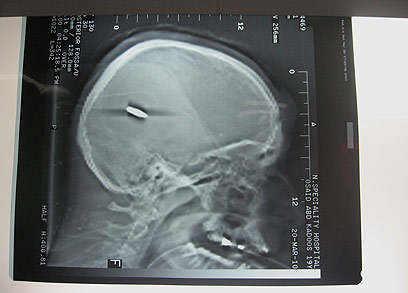

Military officials say that troops did not use live ammunition during the confrontation but Nablus doctor Mahmoud Qaadan, who treated Qadus at Rapidia hospital, told Ynet that the findings were conclusive: « We had an entry and exit of a bullet. We do not have a bullet, but this type of injuries with entry and exit wounds are only created by live ammunition and not by rubber-coated bullets. »

The X-rays done at the hospital left no room for doubt regarding the use of live fire in the incident, the Palestinian doctor said. A B’Tselem investigator who arrived at the hospital also claimed that the X-rays proved that the teen was killed by live ammunition and not by rubber bullets.

He added that he had a copy of an X-ray of the 17-year-old who was critically wounded that showed that he had been shot in the head with live ammunition. B’tselem made an identical argument.